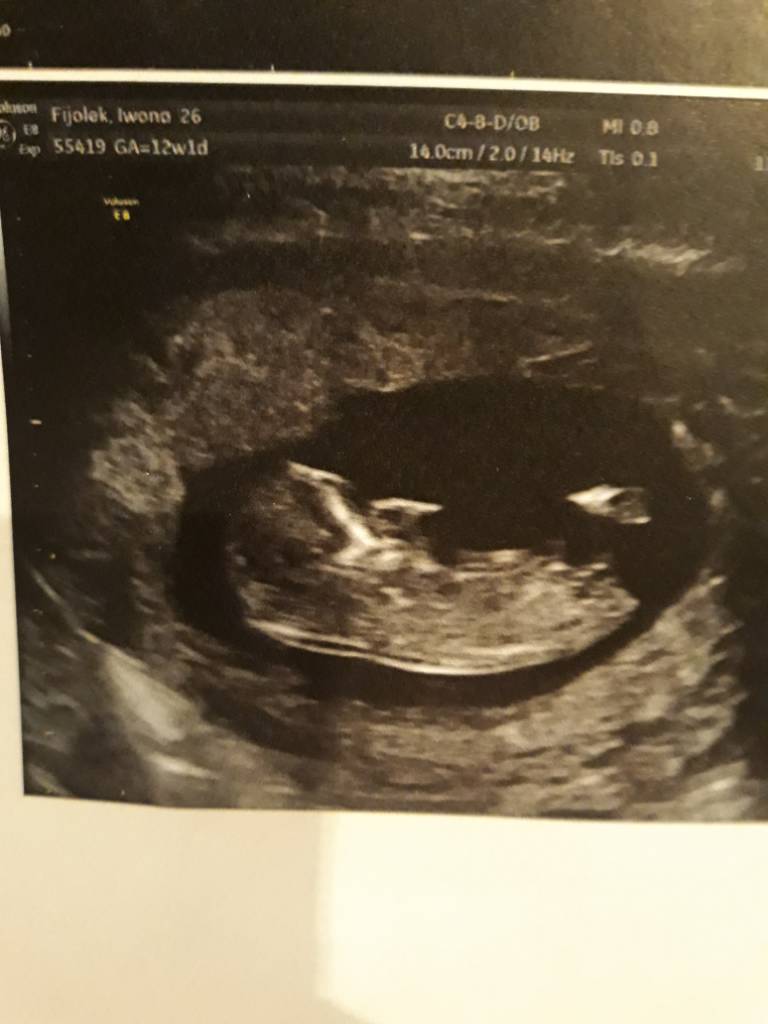

A no i dolaczam zdjecia moich Kabanoskow - jeden leniuszek ladnie pozowal a drugi wyglada jak kosmita bo sie ruszal , dzis tez do mnie machal !

A no i dolaczam zdjecia moich Kabanoskow - jeden leniuszek ladnie pozowal a drugi wyglada jak kosmita bo sie ruszal , dzis tez do mnie machal !ale z dzis zdjec nie mam bo to byl szybki.poglad ze wzgledu na upadek... aaa plecy bola ;(